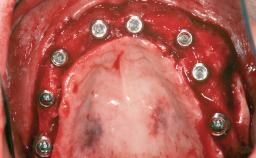

# of Implants 8

Type of Implants Reduced-Diameter|Two-Piece

Bone Augmentation Horizontal|Sinus Floor Elevation|Staged|Vertical

Augmentation Materials Autogenous chips|Autogenous block(s)

Bone Volume Deficient vertically or deficient vertically AND horizontally